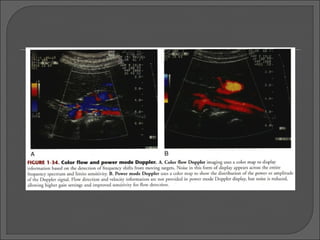

Color Doppler - forma mais comum de US Doppler utilizada é a formação da imagem com Doppler com fluxo colorido  A informação do fluxo é mostrada como uma característica da própria imagem.  Alvos estacionários fornecem a base da imagem em modo-B. A fase do sinal fornece informações sobre presença e direção do movimento em relação ao transdutor e o grau de saturação da cor é usado para indicar a velocidade relativa do movimento das hemáceas.

As imagens coloridas não são imagens de fluxo ou de velocidade, mas sim mudanças da frequência Doppler, que são decodificadas pelo equipamento, que nos apresenta um mapa das velocidades e direções do fluxo.  A cor é, portanto, um método qualitativo para se avaliar a presença, direção, velocidade e característica do fluxo.  O fluxo se apresenta em diferentes cores, dependendo da direção e velocidade. Por convenção:  cor vermelha = fluxo aproximando-se do transdutor;  cor azul = fluxo afastando-se do transdutor;

• 14.

Power Doppler – mapa colorido que mostra a potência integrado do sinal Doppler em vez da variação da frequência. Indica a amplitude do sinal Doppler.  Indica a presença ou ausência de fluxo.  Não fornece informações relacionadas à direção ou à velocidade do fluxo.